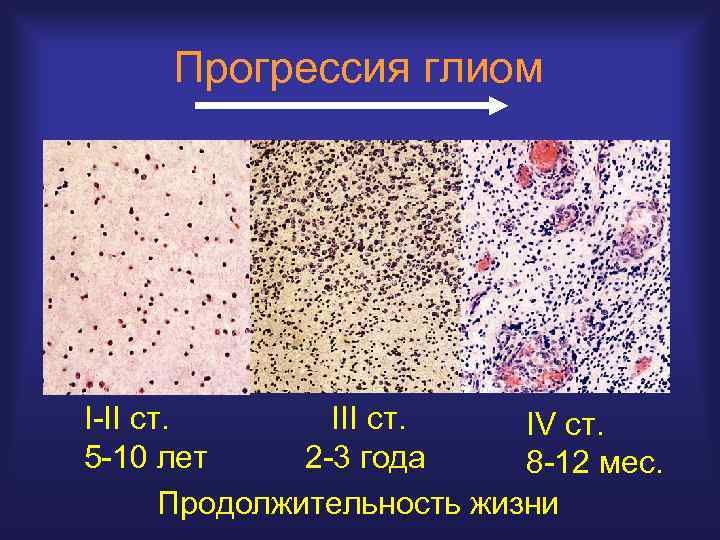

Прогрессия глиом I-II ст. IV ст. 5 -10 лет 2 -3 года 8 -12 мес. Продолжительность жизни